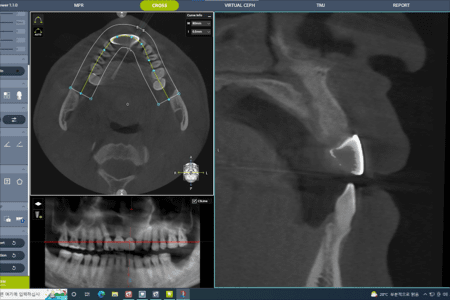

CT 촬영

모의수술

디자인

(디자인)